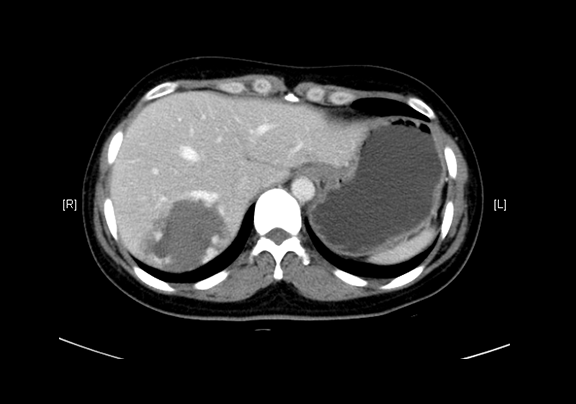

静脉期